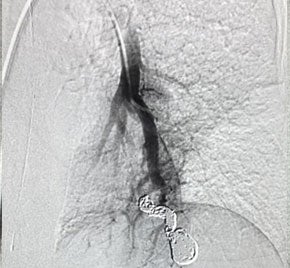

Patient presented to the ER with bilateral AVMs. Multiple right-sided AVMs were treated and the patient scheduled future treatment of the left-sided AVM.

An 8 F guiding catheter, 4 F diagnostic catheter and a Direxion HI-FLO microcatheter were placed in the left-sided AVM. Two 14 mm Embold Fibered Coils were placed in the 11 mm nidus, and 10 mm and 8 mm coils were placed in the feeding vessel.

300x300 Visualizing the bleed​